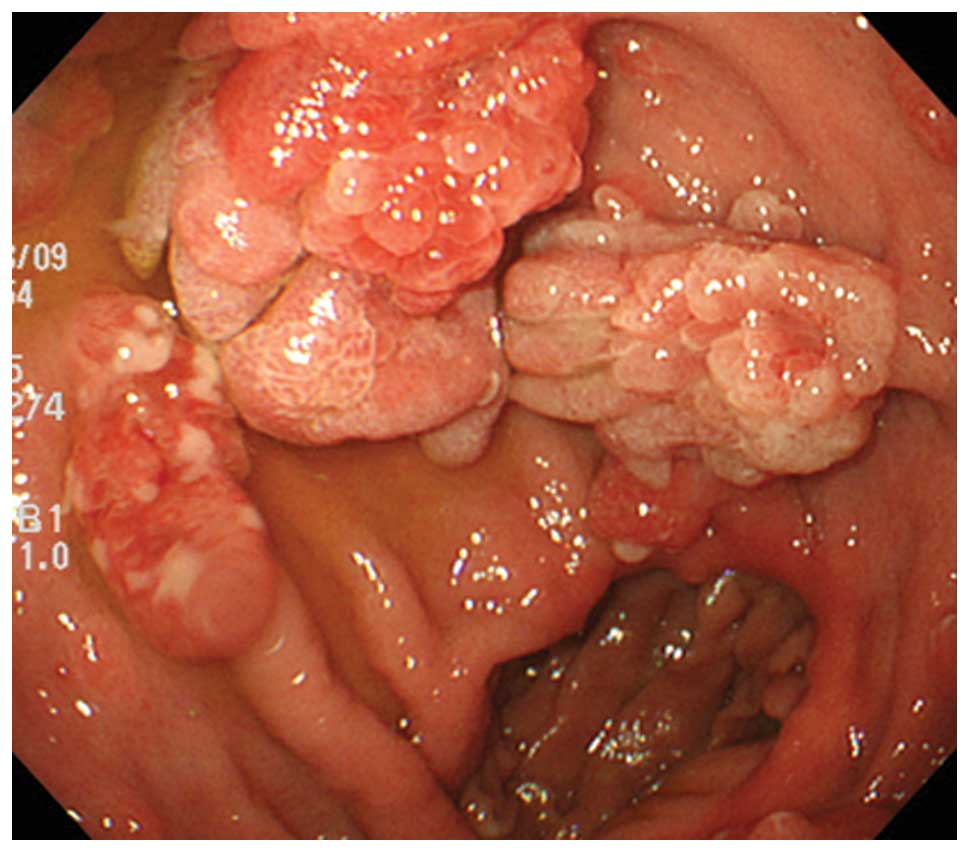

The patients consisted of four males and two

females, ranging in age between 65 and 78 years (mean age, 70

years). Endoscopic assessment revealed solitary (four cases) and

multiple (two cases) pedunculated polyps in the gastric mucosa

(Fig. 1). The patient